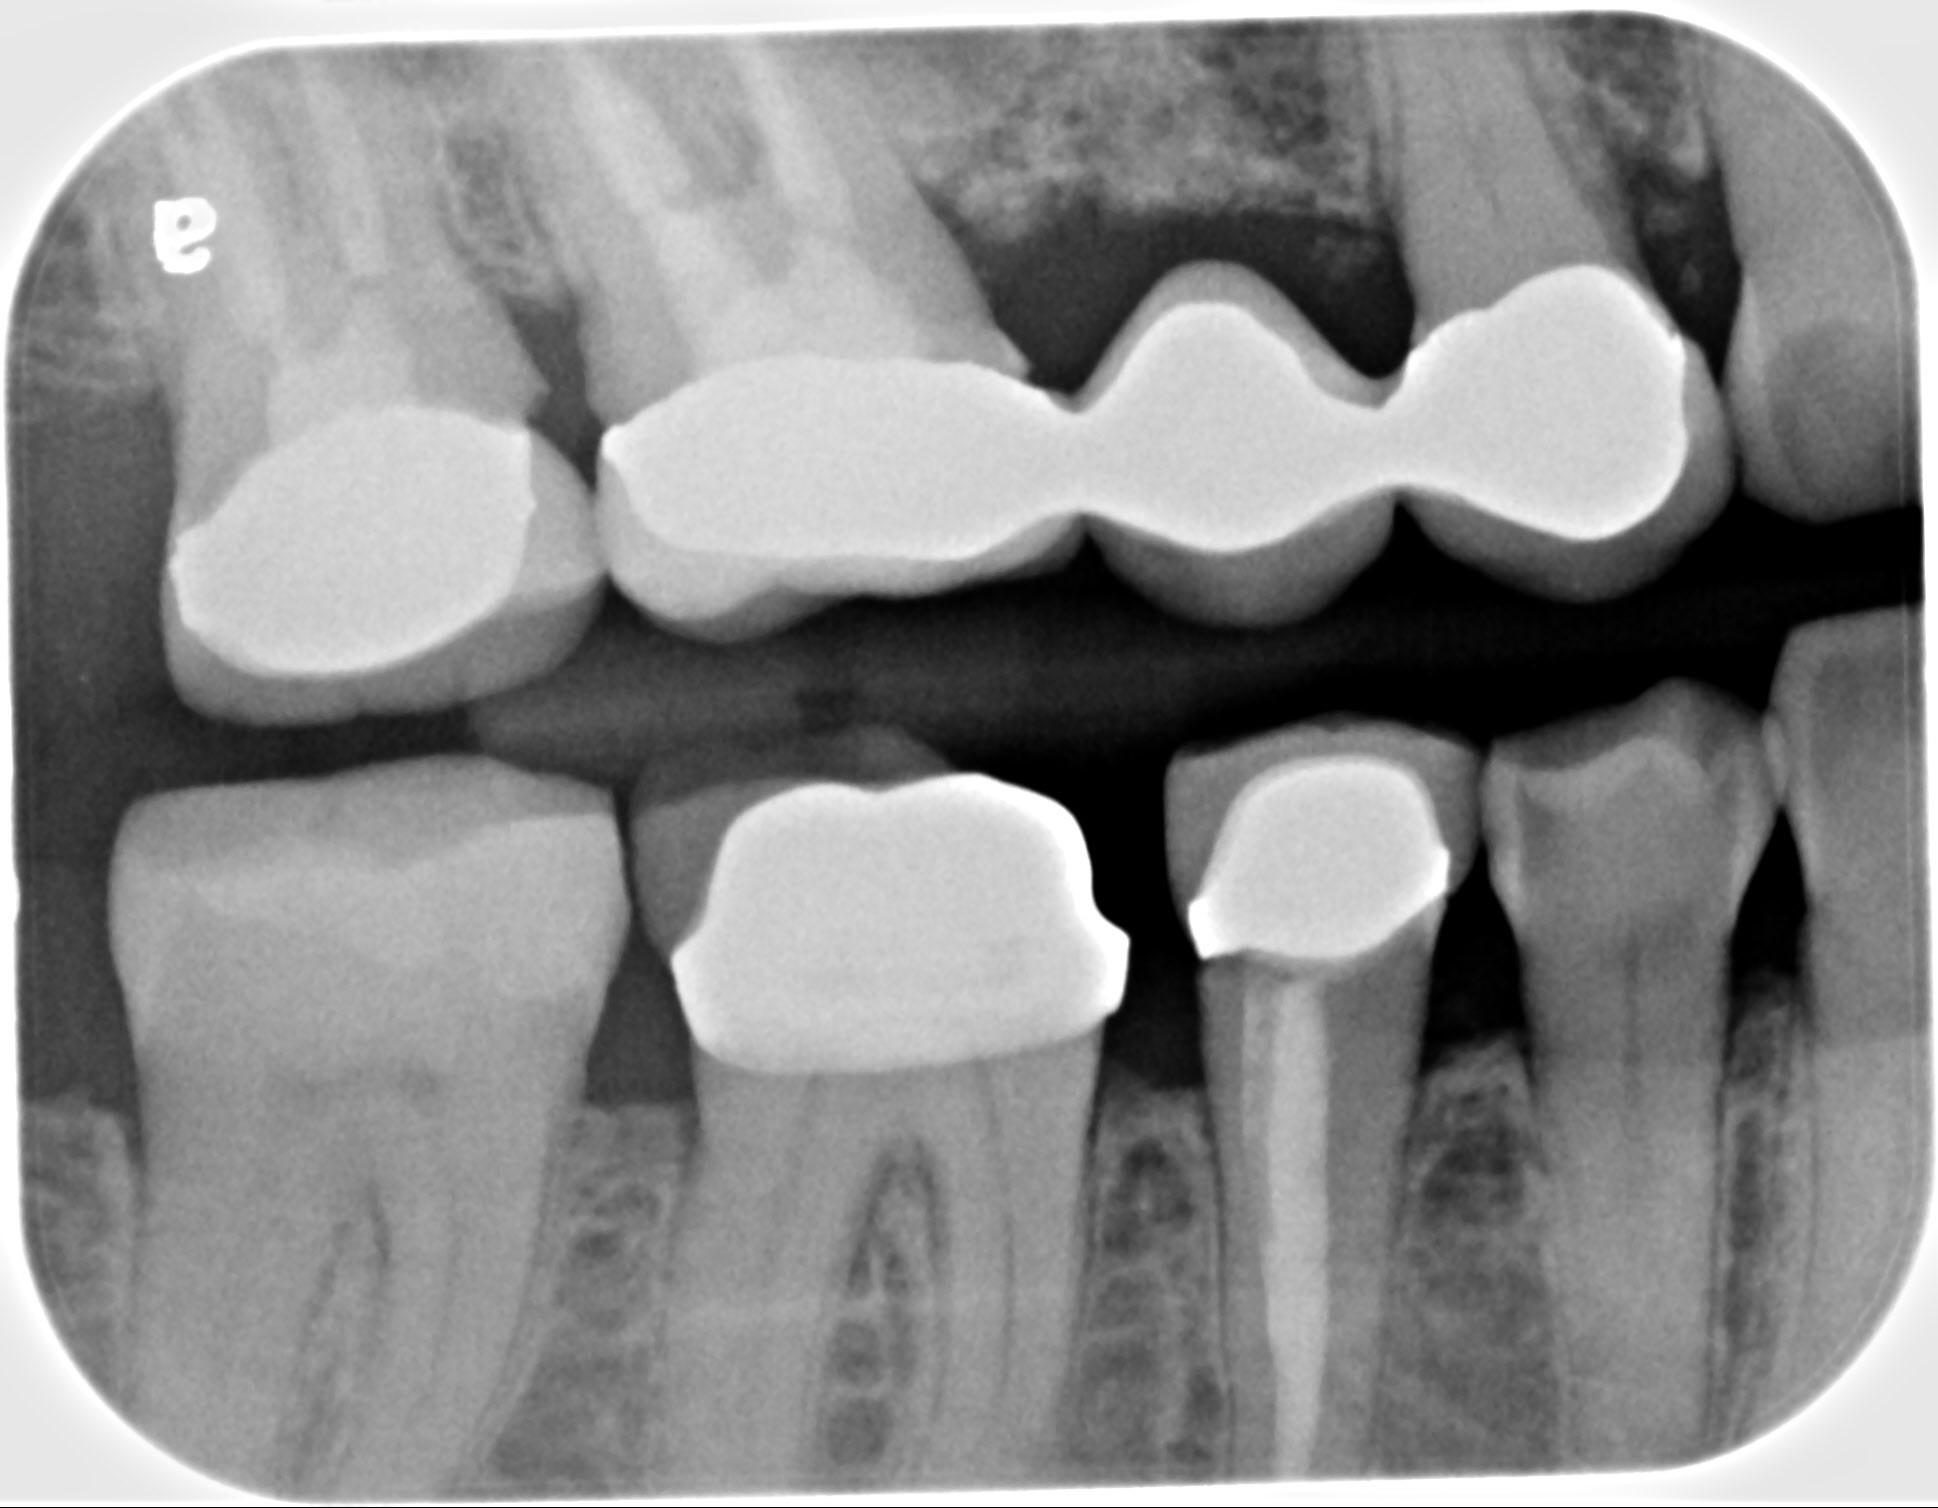

21. What option can be selected for the restoration on upper jaw?